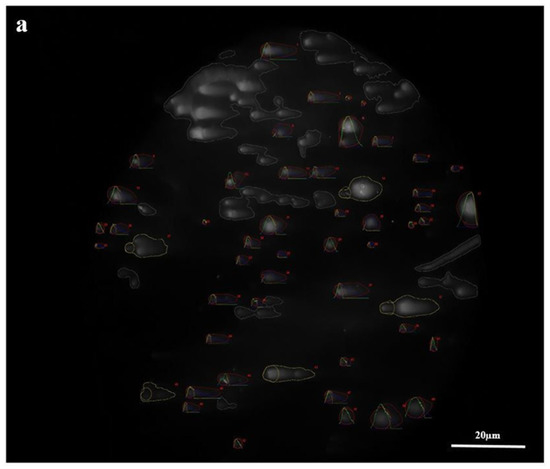

The comet assay results showed that tail deformations in the COVID-19 group were definite compared with the control group. To provide an objective comparison, damage samples were selected (Figure 3).

Figure 3.

Comet assay distribution of the COVID-19 and control groups (×1000 magnification). The damaged samples of the COVID-19 (a) and control (b) groups.